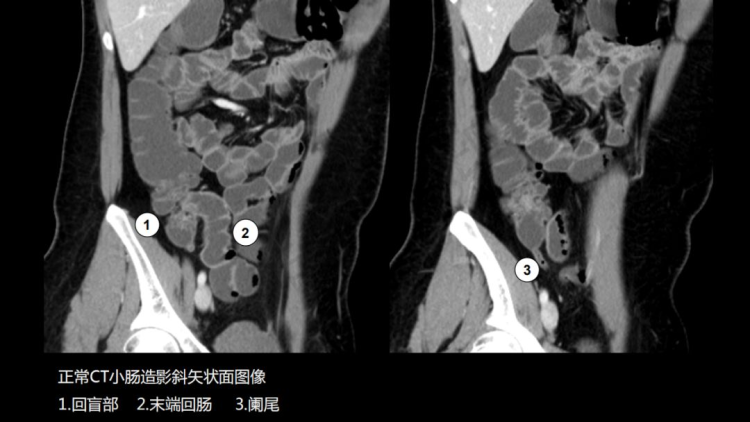

CT小肠造影(CT enterography,CTE)是患者口服或经小肠导管注入对比剂使小肠腔充盈足量对比剂后,经多排螺旋CT增强扫描,并将图像进行后处理,使肠腔、肠壁、肠系膜、腹腔内血管、后腹膜及腹内实质脏器多方位显示出来的技术。临床证明,CT小肠造影(CT enterography,CTE)可精确的判定小肠肿瘤的数目,监测出小肠早期肿瘤,可作为小肠肿瘤定位及诊断的首先检查方法。

CTE简便易行,无明显并发症,不仅能观察肠腔、肠壁、肠外淋巴结、肠系膜、肠系膜血管关系以及毗邻结构等,还可以精确显示粘膜病变、肠壁增厚及肠外并发症,可准确判断小肠肿瘤的浸润深度。适用于多种小肠病变,全腹部扫描能及时发现肿瘤转移情况,有助于临床更准确的把握肿瘤术前分期,能够为患者制定最优治疗方案,带来更好的预后。